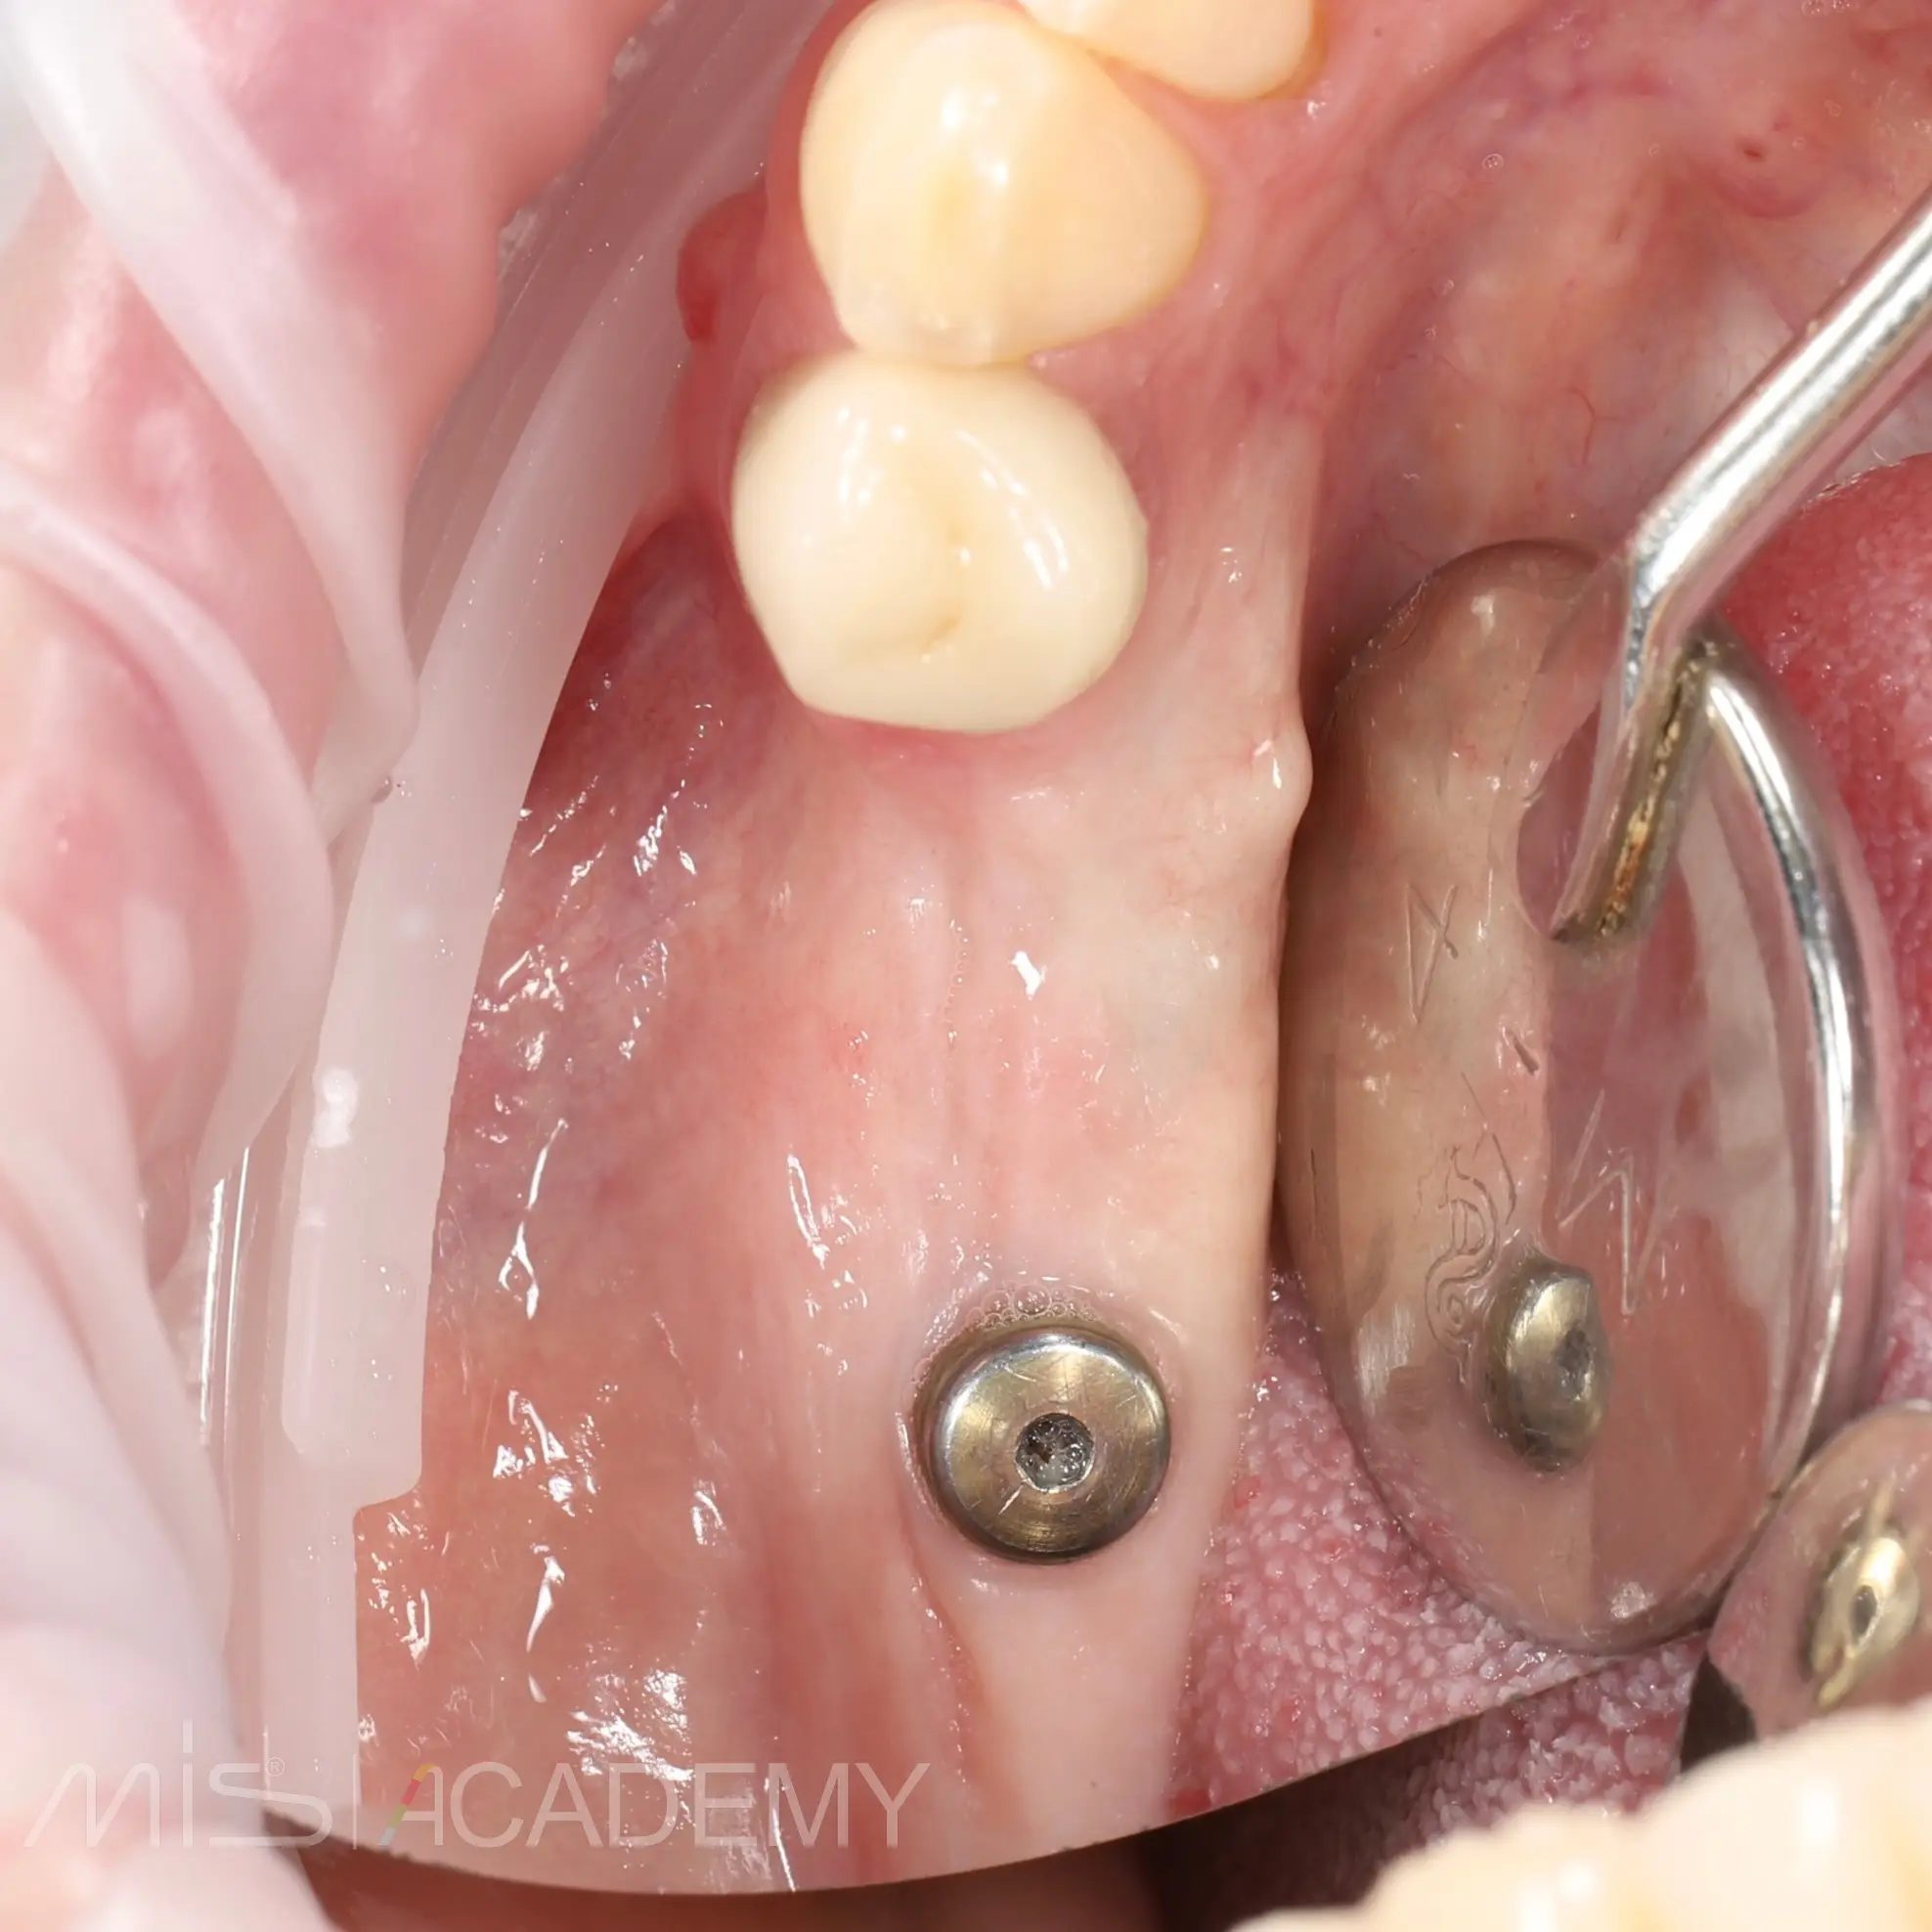

К нам обратилась пациентка с жалобами на боль и подвижность зуба на НЧ справа. Зуб 4.4: под коронкой, свищ, потеряна вестибулярная стенка из-за хронического воспалительного процесса. Имплантат в области 4.7 был ранее установлен, но не хватало объема мягких тканей.

— Через 4 месяца провели пластику мягких тканей для создания объема и сняли винт.

— Установили МЮ для дальнейшего протезирования.